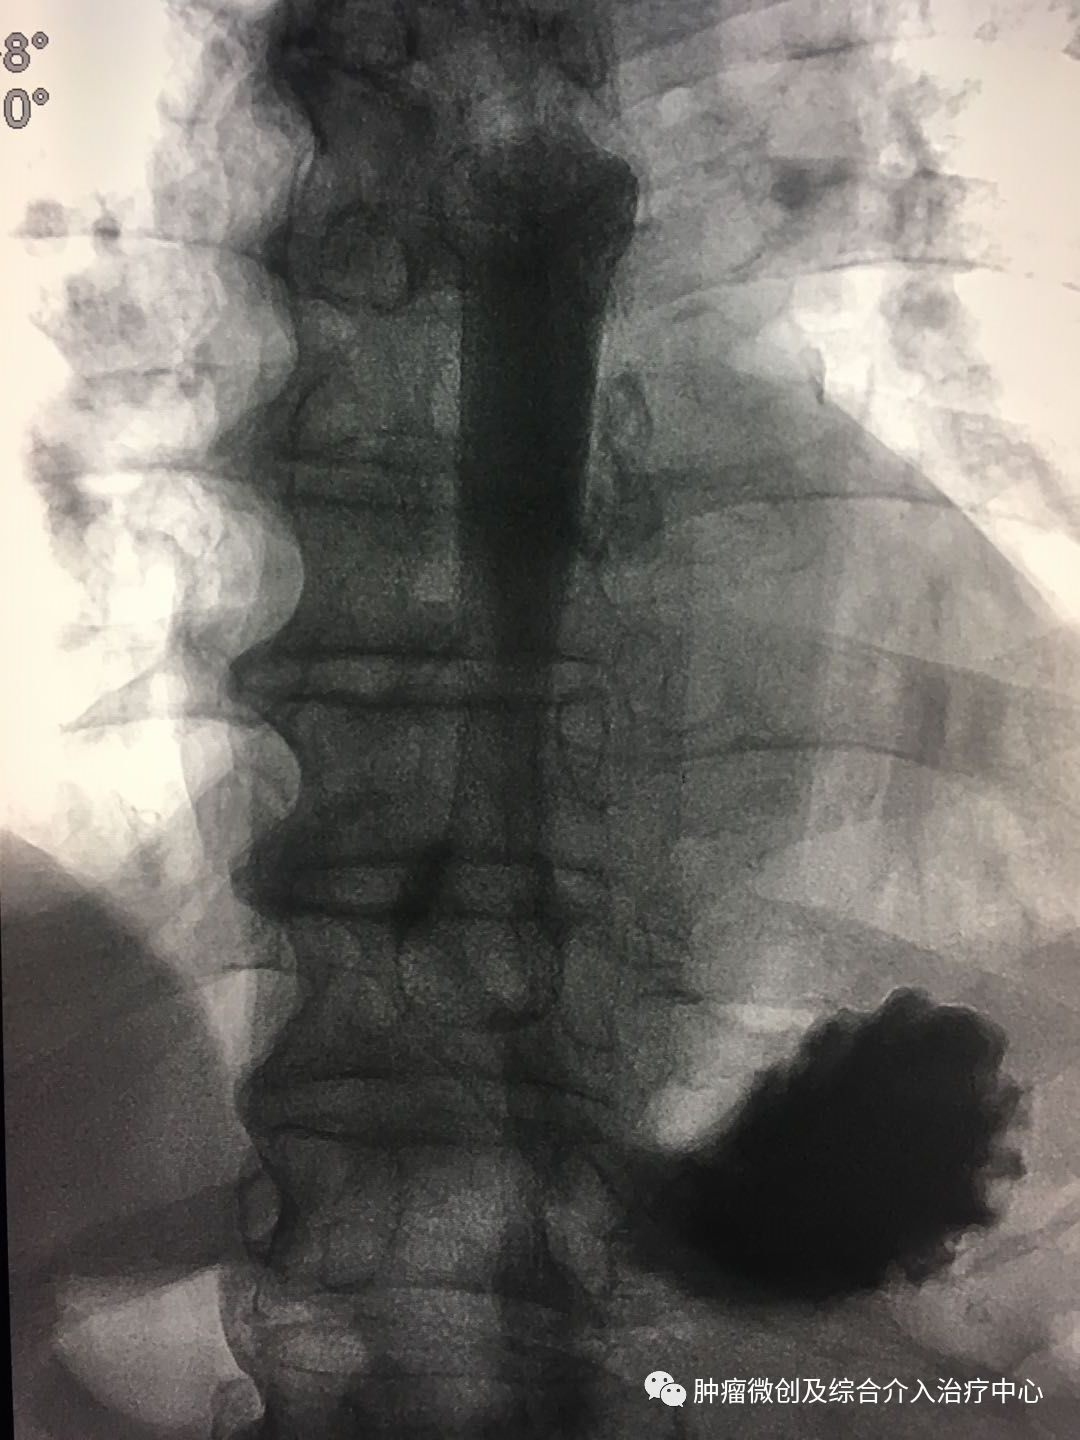

术前造影:食管下段明显狭窄。

在透视下放入食道支架

术后患者即刻可进食。